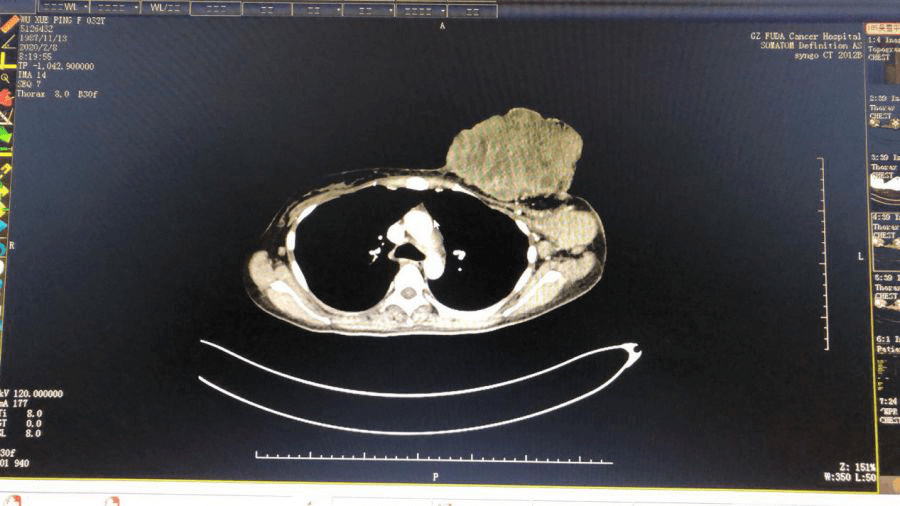

2月8日,星期六,放射科医护人员主动放弃休假时间赶回医院为帮助李梅进行一系列超声及CT检查,报告显示:软组织肿块呈现形态不规则,大小约17.1×8.1×18.9cm,双侧腋窝、左侧锁骨下区及纵膈内可见多个肿大及稍大淋巴结,左侧腋窝较大者约6.3×4.4×5.6cm,双肺多发转移瘤,较大位于右肺中叶,大小约2.3×2.7cm 。